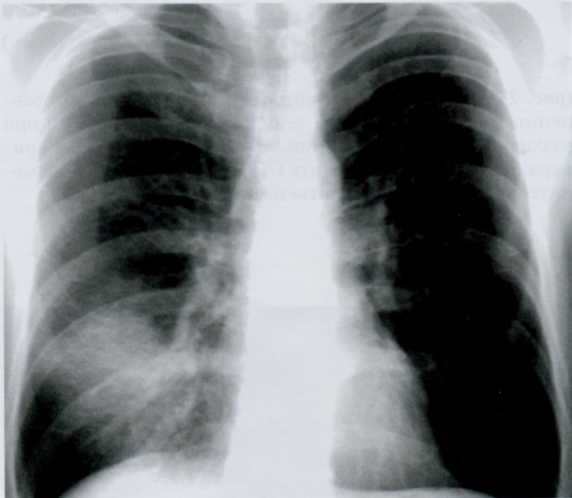

Данная рентгенография грудной клетки ребенка выполнена “на крике”. Что Вы можете отметить?

Оцените признаки наличия полнокровия/инфильтрации/аспирации мекония.

На данный момент обучения, возможно, Вы еще не знакомы с Rx-признаками пневмонии/аспирации мекония, однако визуально посмотрите на снимок и отметитьте некоторые черты, которые притягивают внимание.

Какие-то инфильтраты и полнокровие точно есть. И тут Вы начнете думать: почему? Пациент явно ребёнок. Аспирация? Пневмония?

Мы смотрим снимке ВСЕГДА в контексте клинической картины, но тут просто поразмыслим.

Ниже представлен снимок того же ребенка, который перестал плакать и лаборант успел выполнить повторный снимок.

Мы видим нормальную рентгенограмму грудной клетки (чистые легочные поля), и аэрофагию (18) - воздух в желудке, проглоченный во время плача.

Мораль: необходимо определить в какой фазе дыхания был выполнен снимок + ВСЕГДА иметь клинический контекст.